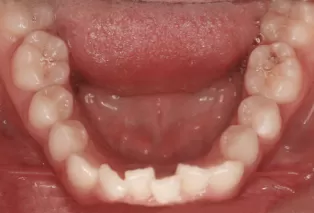

Photos intra-orales